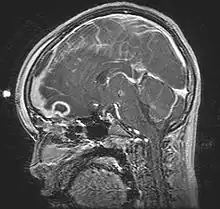

Pott's puffy tumor, spreading towards person's brain. MRI, T1, sagittal, gadolinium contrast.

Pott's puffy tumor, first described by Sir Percivall Pott in 1760, is a rare clinical entity characterized by subperiosteal abscess associated with osteomyelitis. It is characterized by an osteomyelitis of the frontal bone, either direct or through haematogenic spread. This results in a swelling on the forehead, hence the name. The infection can also spread inwards, leading to an intracranial abscess. Pott's puffy tumor can be associated with cortical vein thrombosis, epidural abscess, subdural empyema, and brain abscess.

Although it can affect all ages, it is mostly found among teenagers and adolescents. It is usually seen as a complication of frontal sinusitis or trauma. Medical imaging can be of use in the diagnosis and evaluation of the underlying cause and extent of the condition. Ultrasound is able to identify frontal bone osteomyelitis,[1] while computed tomography (CT) can evaluate bony erosion, and along with magnetic resonance imaging (MRI), can better appreciate the underlying cause and extent of possible intra-cranial extension/involvement.[2][3]